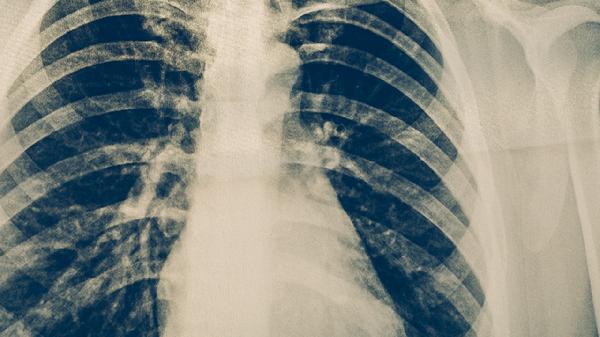

X光胸透可以检查出部分肺癌,但存在漏诊概率。肺癌筛查主要依赖低剂量螺旋CT,X光胸透对早期肺癌的检出率较低,可能遗漏小结节或特殊位置的病灶。

X光胸透作为一种基础影像学检查,能够显示肺部较大肿块、肺门增大、胸腔积液等中晚期肺癌的典型表现。对于直径超过2厘米的中央型肺癌,尤其是伴有阻塞性肺炎或肺不张的情况,胸透检查通常能发现异常阴影。胸透的优势在于操作简便、辐射剂量低且成本较低,适合大规模体检筛查。

胸透对早期周围型肺癌的检出率不足30%,可能漏诊小于1厘米的肺结节、磨玻璃样病变以及被心脏或横膈遮挡的病灶。部分肺泡癌或沿支气管壁生长的肿瘤在胸透中仅表现为局部纹理增粗,容易与肺炎或结核混淆。对于高危人群如长期吸烟者,胸透阴性结果不能完全排除肺癌可能。

建议40岁以上吸烟人群每年进行低剂量螺旋CT筛查,该技术能发现90%以上的早期肺癌。若胸透发现可疑阴影,需进一步通过增强CT、PET-CT或支气管镜检查明确诊断。同时应结合肿瘤标志物检测和临床表现综合判断,避免单一依赖胸透结果延误治疗时机。